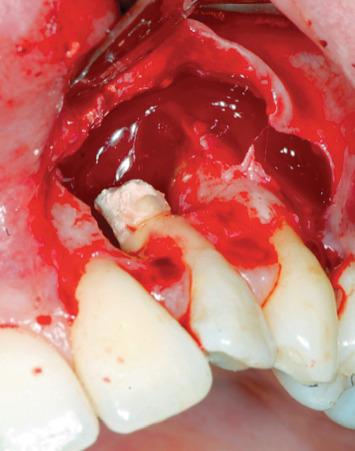

The aim of this case report was to evaluate the efficacy of a new platelet-rich plasma preparation and its regenerative capacity of bone periapical tissue for the treatment of a very compromised endodontic treated tooth, with a periapical lesion of 1.5 cm in diameter, using a pure platelet concentrate. This is made without the use of anticoagulant or any type of activator, e.g., bovine thrombin, calcium chloride. For this reason, it has been called "Pure"; it is the B.P.F.C.® Bio-Plasma® with Pure Growth Factors (BioPlasma®) designed and developed by Dr. Raffaello Viganò. The patient has read and signed a written consent form. The study protocol was approved by the Ethics Committee for Human Studies, University of Varese. X-ray at 2 and 6 months and 4 years after endodontic surgery demonstrated the success of the treatment.

本病例报告的目的是评估一种新型富血小板血浆制剂的疗效及其对根尖周组织的再生能力,该制剂为纯血小板浓缩物,用于治疗一颗根管治疗后严重受损且根尖周病变直径达1.5厘米的牙齿。该制剂的制备不使用抗凝剂或任何类型的激活剂,如牛凝血酶、氯化钙。因此,它被称为“纯”;它是由拉斐尔洛·维加诺博士设计和研发的含有纯生长因子的B.P.F.C.®生物血浆®(BioPlasma®)。患者已阅读并签署了书面知情同意书。该研究方案已获得瓦雷泽大学人体研究伦理委员会的批准。根管治疗术后2个月、6个月和4年的X线检查显示治疗成功。